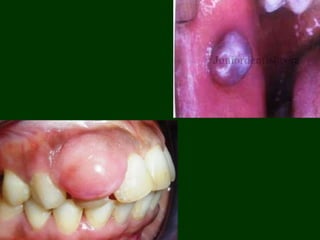

CLINICAL FEATURES

• Age: 2 to 82 years, with a mean of 35 years.

• Sex: Female

• Site: The buccal mucosa > retromolar area region > premolar

region > pterygoid and masseteric muscle > lingual alveolar

mucosa of the edentulous molar region > tongue> maxilla >

hard palate.

• In some cases localized to an extraction site.

• Size ranged from 0.5 to 5cm, rapid growth rate is an

alarming feature of oral IMT reportedly as short as 1 day, with

a majority of lesions of 2 months duration or less

• Well circumscribed, solitary nodule or mass, 40% of the tumor

were designated as firm or indurated and notably demonstrated

ulceration, characterized with varying degrees of erythema.

• Pain was reported with concurrent clinical ulceration. Some

patients experienced trismus

Most lesions are lobular, multinodular or bosselated.